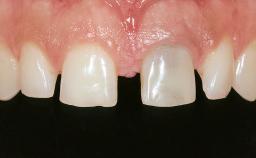

Mauricio Araujo and Flauvia Matarazzo present this straightforward clinical case, demonstrating the potential effect of implant placement depth on the resolution of peri-implant treatment. A 42-year-old systemically healthy female patient, a non-smoker with no history of periodontitis, was treated at the Dental Clinic at the State University of Maringá, Brazil between 2008 and 2009, when she received five implants restored with single crowns at sites 14, 26, 27, 36, and 46. After delivery of the implant-supported prosthetic restorations, the patient was enrolled in the supportive peri-implant therapy (SPiT) maintenance program at the same university.